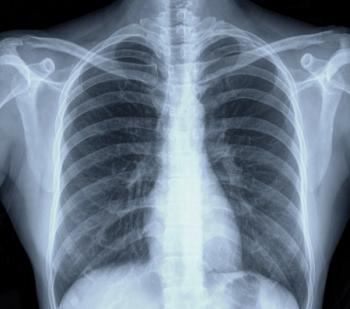

In a cohort study of 496 lung cancer survivors, 11.5% had a recurrence during a five-year follow-up period, and 5.6% had cancer outside the lungs.

Researchers found that less than half (43.8%) of the patients underwent surveillance imaging consistent with recommended guidelines.